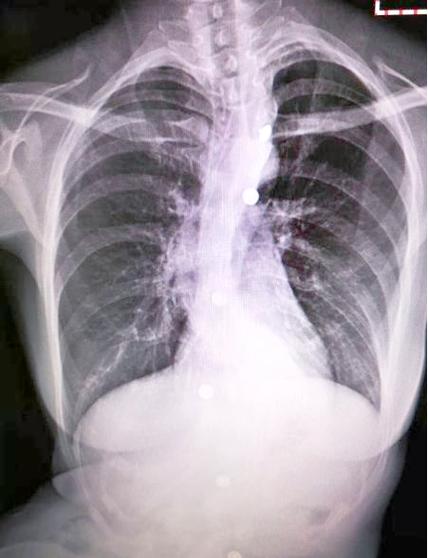

(图片来源网络,侵删)